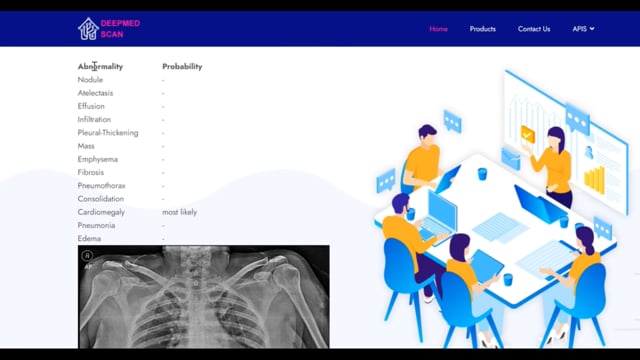

DeepInfinity.AI specializes in using advanced Generative AI and ML technologies to transform healthcare diagnostics and patient care. Our platform applies generative AI models for deep and accurate analysis of medical data, offering a range of predictive and diagnostic tools. These tools are designed to support healthcare professionals in making faster, more accurate diagnoses, thereby enhancing the overall quality of patient care. DeepInfinity.AI uses the advanced Generative AI technology to help Doctors, Hospitals and Diagnostic Centers & Labs etc.